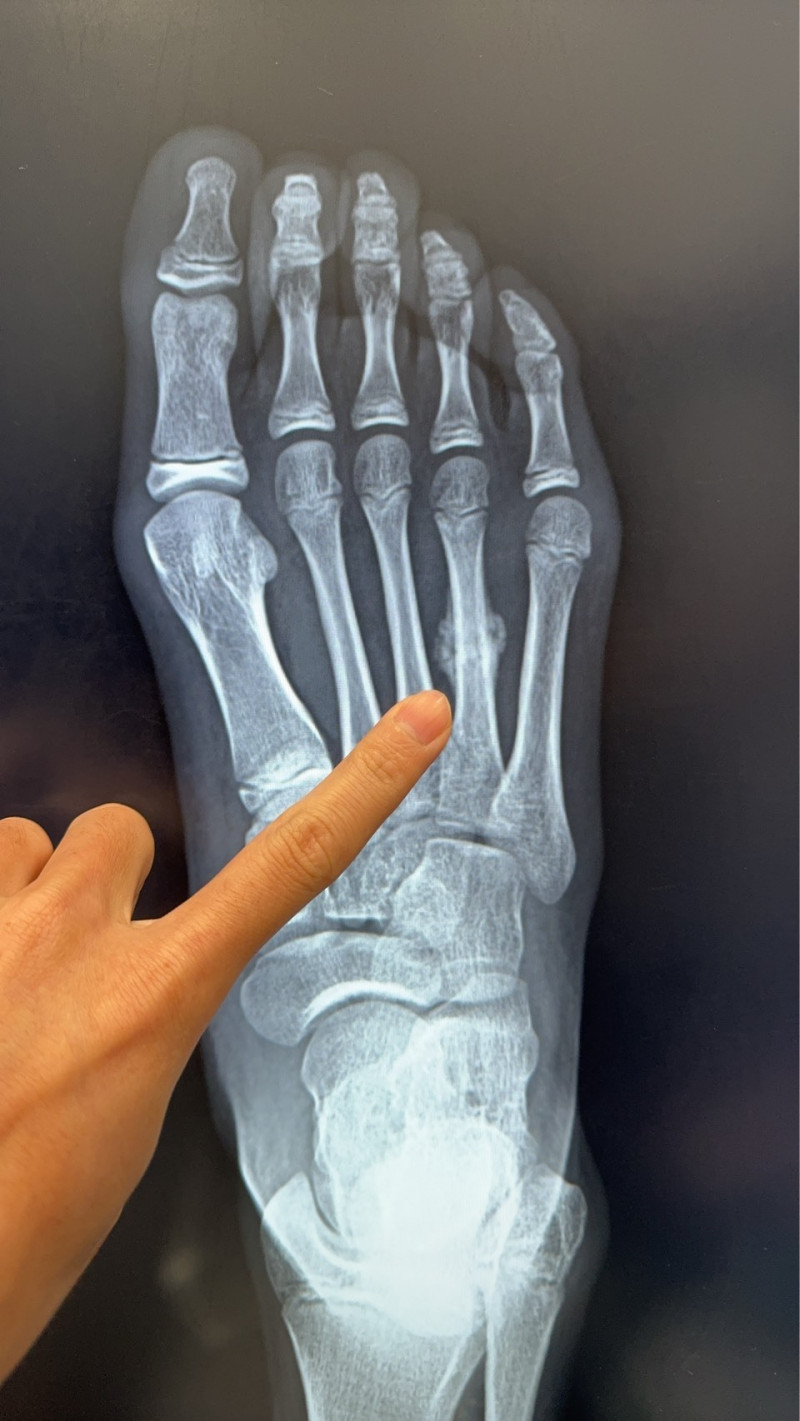

〔記者王俊忠/台南報導〕在寒暑假家長多會鼓勵孩子參與田徑、球類、游泳等活動,培養運動習慣,減少使用3C。但運動帶來健康的同時,也暗藏「過度」的風險。骨科醫師陳建宏指近日診所接獲1名11歲女學童就醫個案,女童因在暑期密集參加田徑與球類訓練,右腳掌疼痛兩週未緩,檢查後確診為「蹠骨應力性骨折」,且已出現癒合跡象。

陳建宏說明,蹠骨位於腳掌前端,承受人體走路、跑跳時的主要壓力。當骨頭長期反覆承受過大的應力,缺乏足夠休息與修復時間時,就可能出現顯微的骨折,即是所謂「應力性骨折」。

這與一般一次性外力造成的骨折不同,應力性骨折大多是長時間累積而成,初期症狀不明顯,易被誤以為是一般拉傷或扭傷。就像這位11歲女童,在問診時說已經不舒服兩週,本以為只是單純扭到,沒想到卻是骨折了!